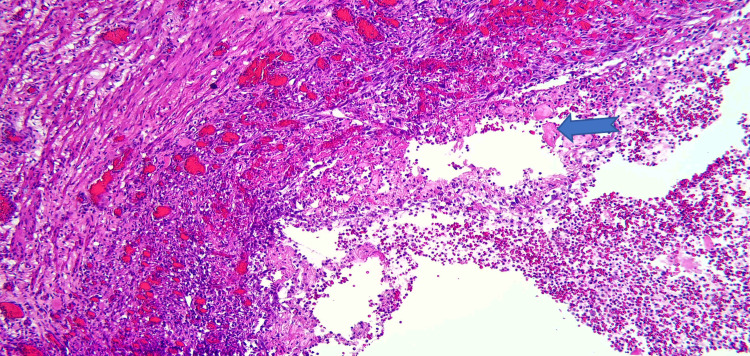

Due to the patient’s symptoms, risk factors, and degree of obstruction, these findings were concerning for possible metastasis. Both gastroenterology and general surgery were consulted for consideration of either endoscopic ultrasound with fine-needle aspiration or open surgical biopsy of the mass. Ultimately after multidisciplinary discussion, general surgery was planned for a biopsy of the mass and management with PD. Pathology revealed Brunner gland hyperplasia, pseudocysts with granulation tissue, chronic inflammation, and proteinaceous material consistent with GP (Figures 6–8). MRI of the liver deemed the lesion to be a benign hemangioma. Additionally, cluster of differentiation 31 (CD31), human herpesvirus-8 (HHV-8), and Helicobacter pylori immunostaining were all negative. He did well postoperatively and was discharged with bilateral Jackson-Pratt drains. At his outpatient follow-up, he endorsed improvement in appetite and resolution of his symptoms.